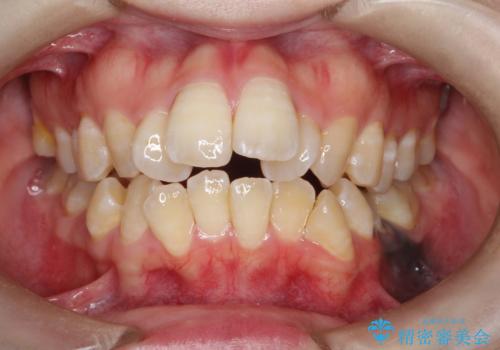

前歯の隙間を閉じたい インビザラインによる矯正

- 上下の前歯に隙間があるとのことで来院されました。

インビザラインにて隙間を閉じる矯正を行いました。